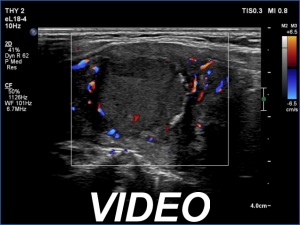

Clinical presentation: A 66-year-old woman was referred for cytology. The patient felt discomfort in her neck while lying on her left side for a few months.

Palpation: a firm nodule in the left lobe.

Diagnosis: Hashimoto's thyroiditis. Suspicion of follicular cancer.

Frozen section disclosed follicular cancer, therefore total thyroidectomy was performed. The definitive histopathological diagnosis was widely invasive follicular cancer and Hashimoto's thyroiditis.